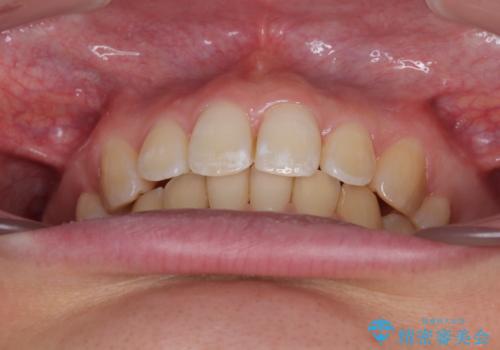

上下の抜歯位置を変えることで、左右ともに理想的な咬み合わせを達成することができました。

横顔の印象はほとんど変わらないものの、唇を閉じたときに前に出ていた下唇が、治療後には少し下がった状態に仕上げることができました。